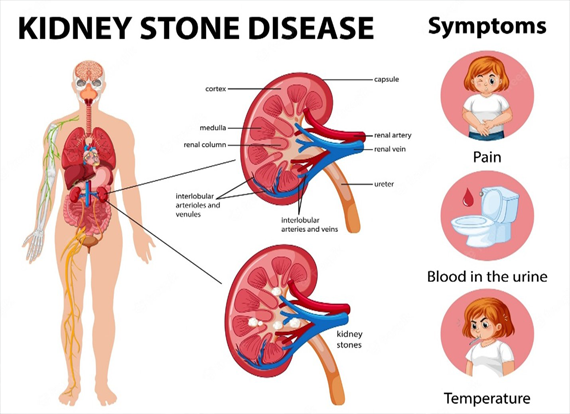

– Chronic renal failure

– Kidney disease